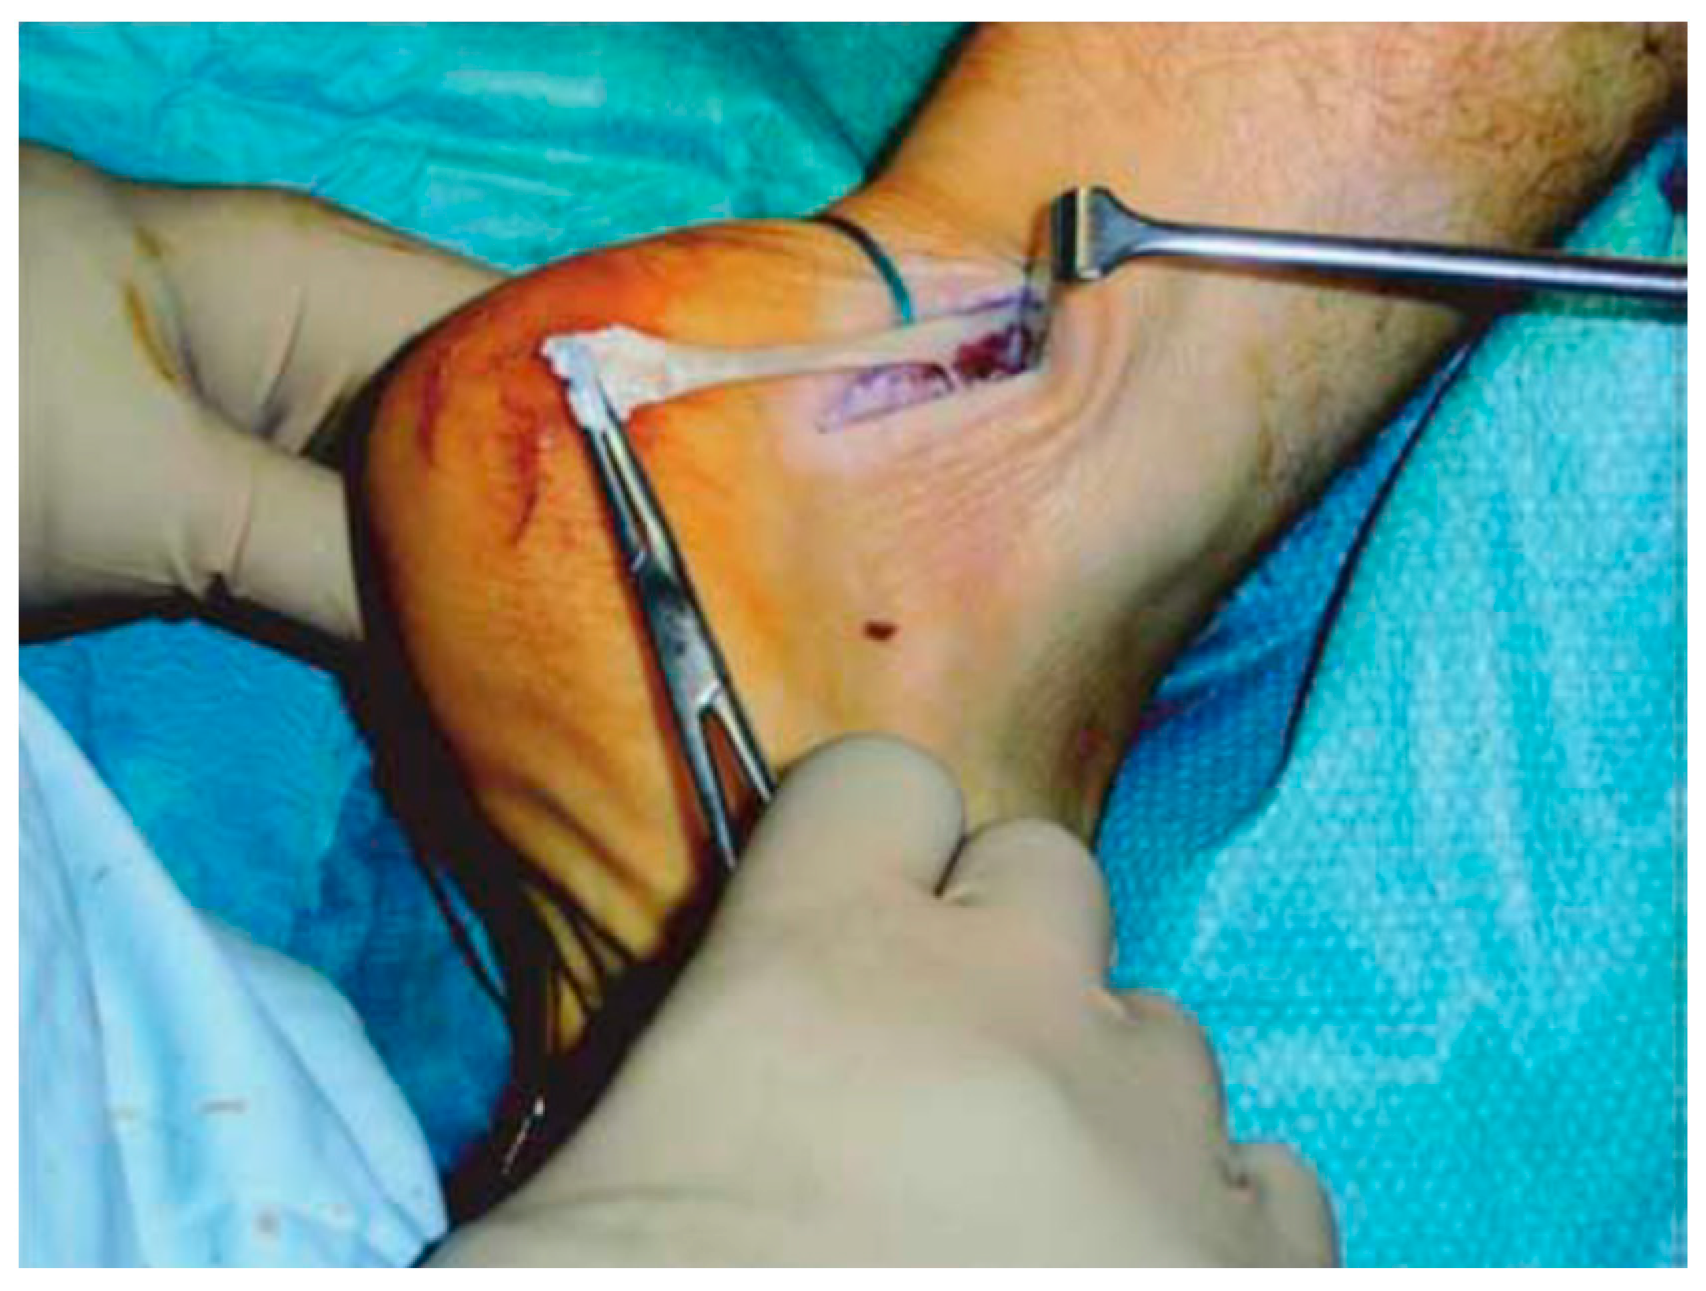

Longitudinal incisions are made from tendon medial size avoiding sural nerve and short saphenous vein injuries [18]. Tendinopathic tissue is identified and removed, and it appear with a disorganised fibre bundles with a “crabmeat” appearance [18]. Any gap can be repaired using a side-to-side repair and can remain unsutured, or if significant loss tissue occurs, a tendon augmentation or transfer can be considered. Peroneus brevis (Figure 7) or flexor hallux longus (Figure 8) tendons are the most frequently used local tendon grafts [43,125,126].

Figure 7.

Photograph showing the peroneus brevis tendon being mobilised and pulled distally after the removal of adhesions and surrounding fibrosis.